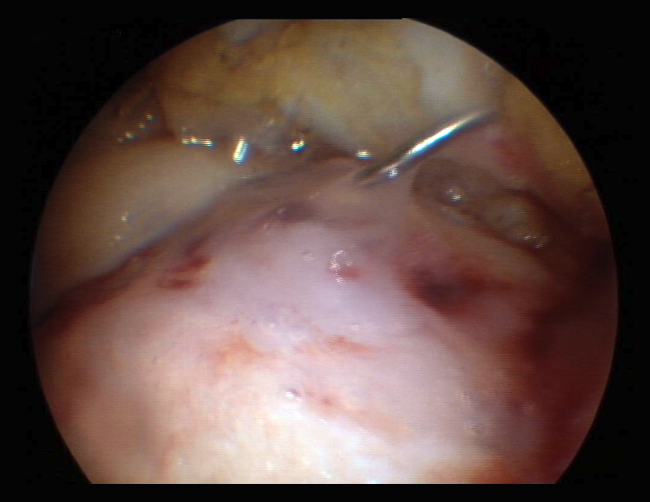

Figure 2. A: arthroscopic appearance of an ulcer with bleeding microfracture orifices; B: appearance of the same zone covered by fibrocartilage 8 months later.